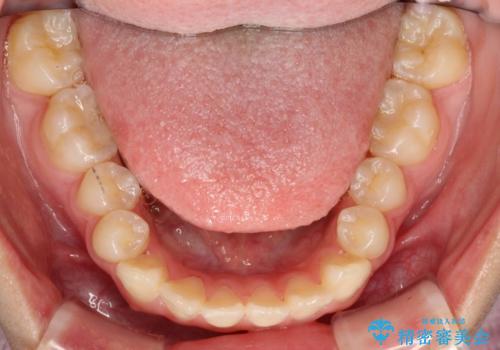

上あごの2番目の歯は矮小歯といって、生まれつき小さい歯となる事がよくあります。

このような場合、矯正によりスペースを集め、本来あるべき形態にセラミックで修正することもできます。

時間はかかりましたが、きれいな笑顔になりました。